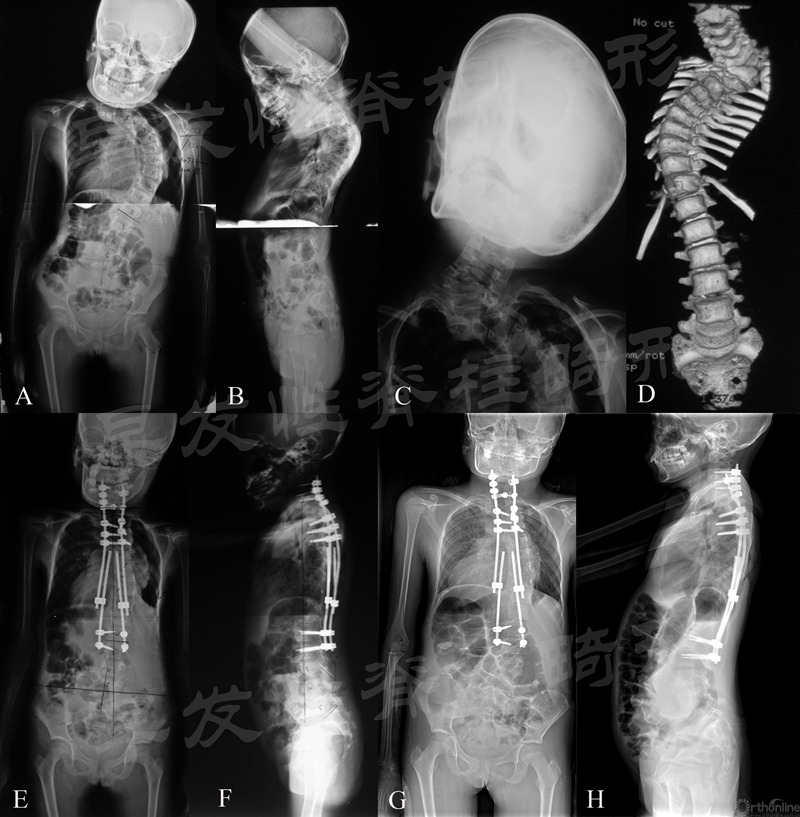

针对此类畸形,北京协和医院仉建国教授团队针对早发、严重僵硬性脊柱侧凸首次提出了截骨短节段融合联合双生长棒的混合技术,其研究结果最早于2014年在Spine发表。7例患者,平均初次手术年龄5.9岁,平均每例患者经历5.3次撑开术。冠状面主弯度数术前为81.4°,术后为30.1°,末次随访时为41.0°;T1-S1每年增长1.23cm;SAL术前为0.87,术后改善至0.95,末次随访时为0.96,截止最近随访无并发症发生(图4~6)。

图4 患儿,女性,8岁。A~D.复杂颈胸段畸形伴胸椎严重侧凸;E、F.行颈胸段截骨短节段融合,远端使用双生长棒控制胸弯;G、H.术后3年提示矫形维持良好

图5 患儿,男性,6岁。A、B、G.严重先天性脊柱侧凸;C、D.行顶椎区截骨短节段融合以及双生长棒矫形;E~H.术后5年随访矫形满意,脊柱明显生长,胸廓发育良好

图6 患儿,女性,4岁。A~C、H.严重先天性脊柱侧凸;D、E.行顶椎区截骨短节段融合以及双生长棒矫形;F~I.术后3年随访矫形满意,脊柱明显生长,胸廓发育良好